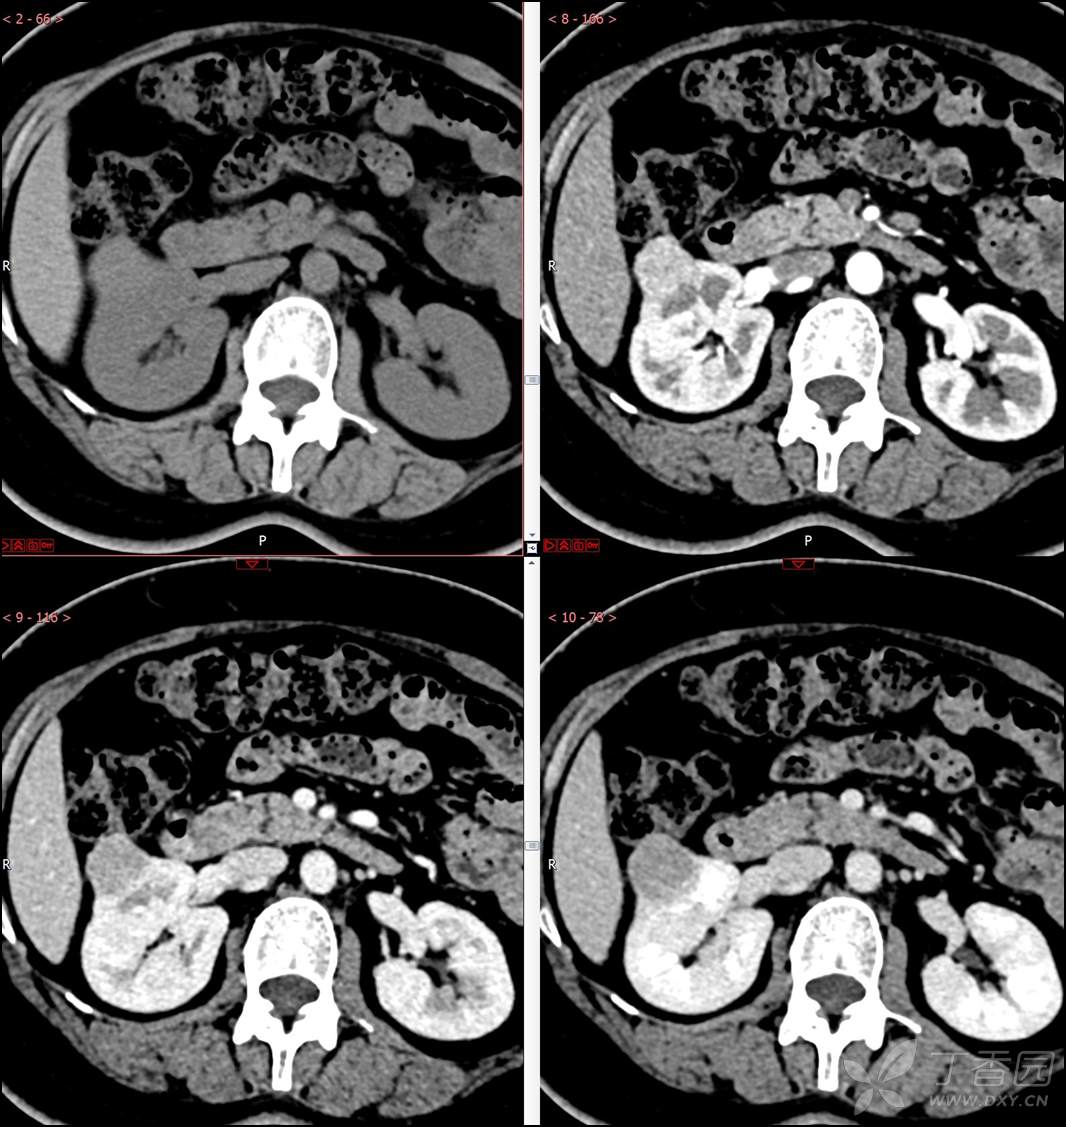

【影诊笔记516】中年女性,检查发现肾占位2周就诊~『嗜酸细胞腺瘤』

主诉:检查发现肾占位2周

简要病史:患者2周前体检发现肾实质性占位,无腰痛,无血尿,无尿频、尿急、尿痛,无发热,在外未行特殊治疗。患者为行进一步治疗就诊于我院,门诊以“肾占位性病变 ”收入我科,患者自发病以来,神志清,精神可,小便如上所述,大便正常,体重无显著变化。